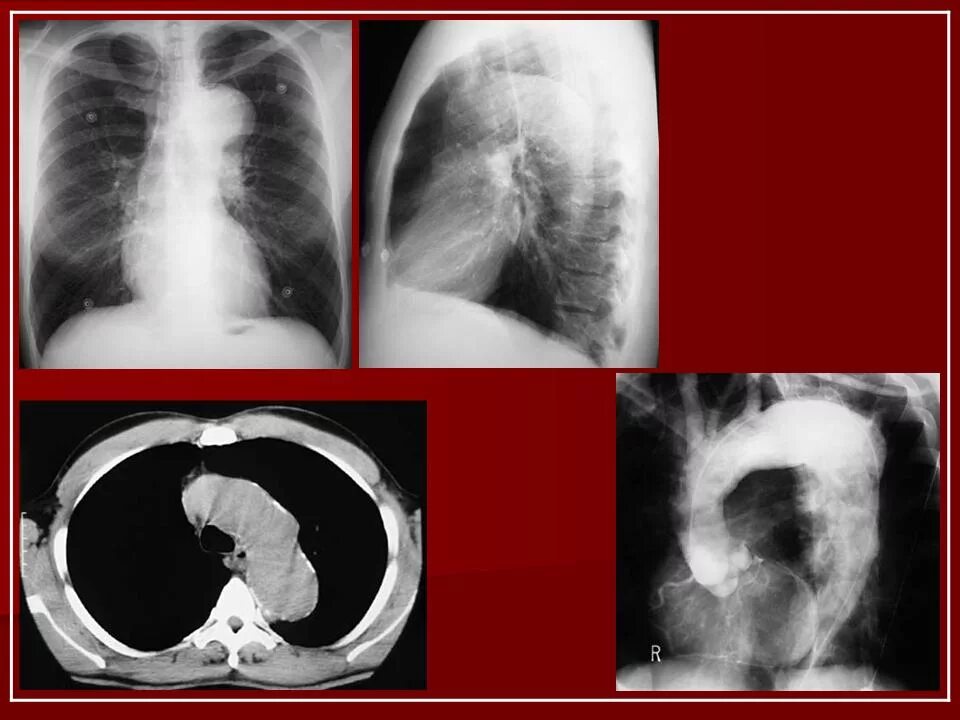

Аневризма нисходящего отдела аорты